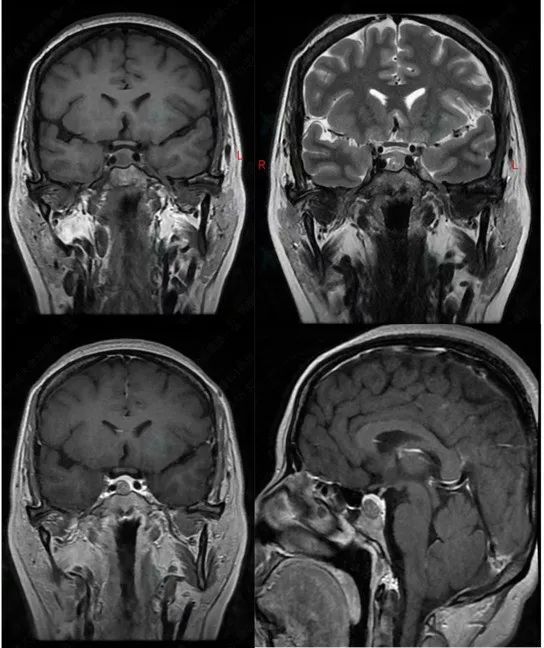

患者术前垂体MRI

纪女士是其中之一,因发现鞍区占位性病变于我院神经外科垂体瘤专病门诊找李奇副主任医师就诊。完善垂体核磁检查后明确诊断为无功能垂体大腺瘤。在收治住院后经全面检查排除手术禁忌症后李奇副主任医师决定采用吲哚菁绿荧光造影辅助经鼻神经内镜下垂体瘤切除术。